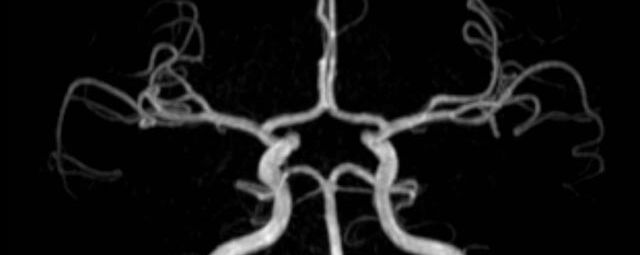

• intrakranielle Gefäße (Abklärung Verschluss, Stenose, Aneurysma)

MR-Angiografie (MRA)

Angiographie ohne Kontrastmittel

• MR-Angiografie ohne Kontrastmittel

• Time of Flight (TOF)-Angiographie

• Phasenkontrastangiographie (PCA). Geeignet zur Quantifizierung Stenose-/Insuffizienzgrad z.B. bei Herzklappen, falls echokardiographisch die Untersuchungsbedingungen eingeschränkt sind.

Je nach Fragestellung und Körperregion Gefäßdarstellung ohne Kontrastmittel bei Kontrastmittelunverträglichkeit oder terminaler Niereninsuffizienz möglich.

Ganzkörper Angiographie mit Kontrastmittel

• MR-Angiographie mit Kontrastmittel

• Erfassung arterieller und venöser Gefäße/Bypässe aller Körperregionen mit 3D-Rekonstruktion

• je nach klinischer Fragestellung zeitaufgelöste MR-Angiographie (4D-MRA) z.B. bei Frage arteriovenöse Fistel/ Shunt oder Darstellung Unterschenkelarterien vor geplanter Bypassoperation.